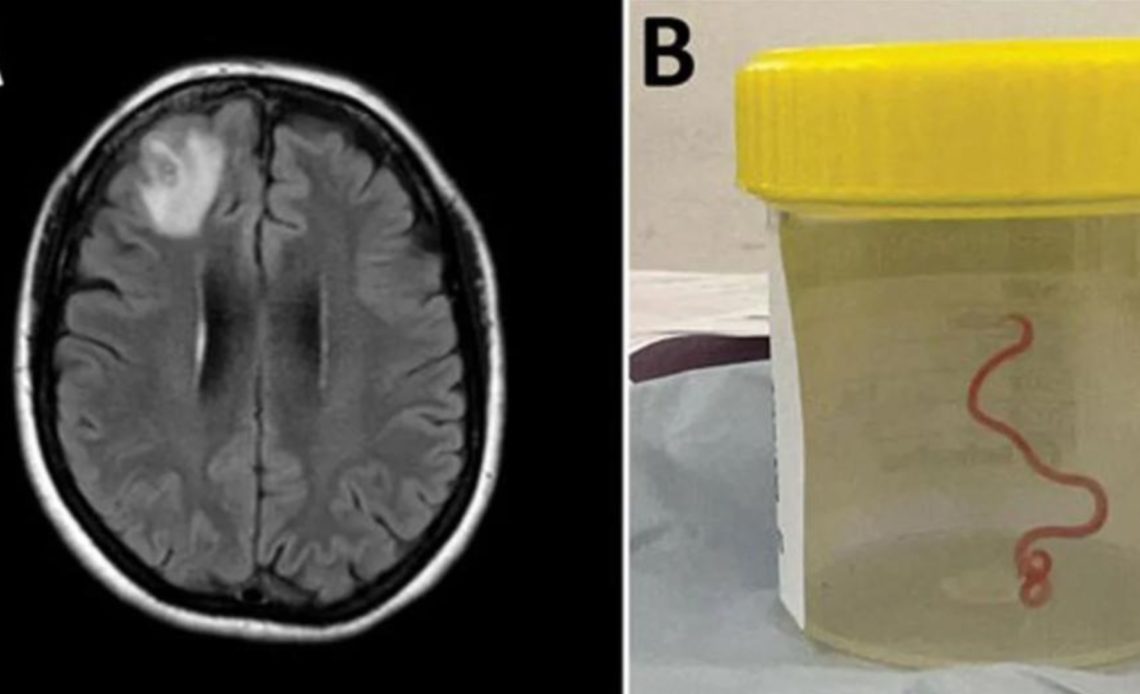

Era una lombriz de ocho centímetros llamada Ophidascaris robertsi, que según investigadores son parásitos comunes en canguros y pitones diamantina pero no en humanos.

«Este es el primer caso humano de una Ophidascaris en el mundo», afirmó el experto en enfermedades infecciosas Sanjaya Senanayake.

«Hasta donde sabemos, es también la primera vez que aparece en el cerebro de una especie de mamífero, humano o no», agregó.